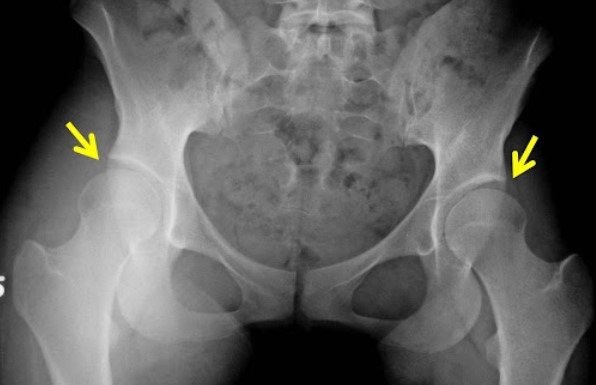

تشخیص دیسپلازی مفصل ران بهوسیله معاینه فیزیکی توسط متخصص ارتوپدی و استفاده از ابزارهای تصویربرداری صورت میگیرد. در نوزادان، پزشکان معمولاً با معاینهی فیزیکی و بررسی وضعیت مفصل ران، دیسپلازی را تشخیص میدهند. اگر مشکوک به وجود دیسپلازی باشند، میتوان از روشهای تصویربرداری مانند سونوگرافی یا اشعه ایکس استفاده کرد.

- رادیوگرافی (اشعه ایکس): در کودکان بزرگتر و بزرگسالان، استفاده از رادیوگرافی به تشخیص مشکلات در مفصل ران کمک میکند.